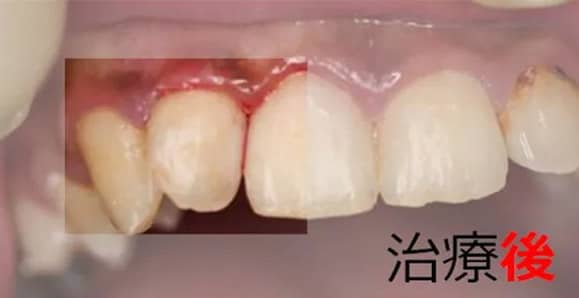

3虫歯/被せもの【虫歯の治療例1】

治療前

治療後